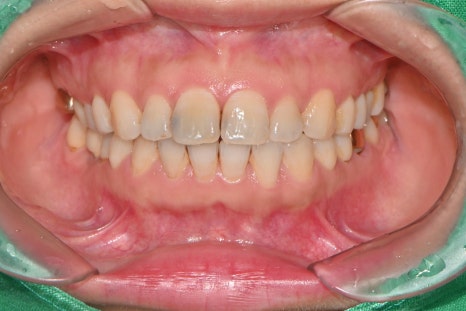

시술 전 파노라마 엑스레이 촬영을 통해 치아와 잇몸 상태를 정밀 검진했습니다.

과거 교정 치료로 인해 치아 안쪽에 부착되어 있던 유지 장치는 시술을 위해 잠시 제거한 후, 라미네이트 부착 완료 후 다시 안정적으로 재부착해 드리는 섬세한 과정을 거쳤습니다.